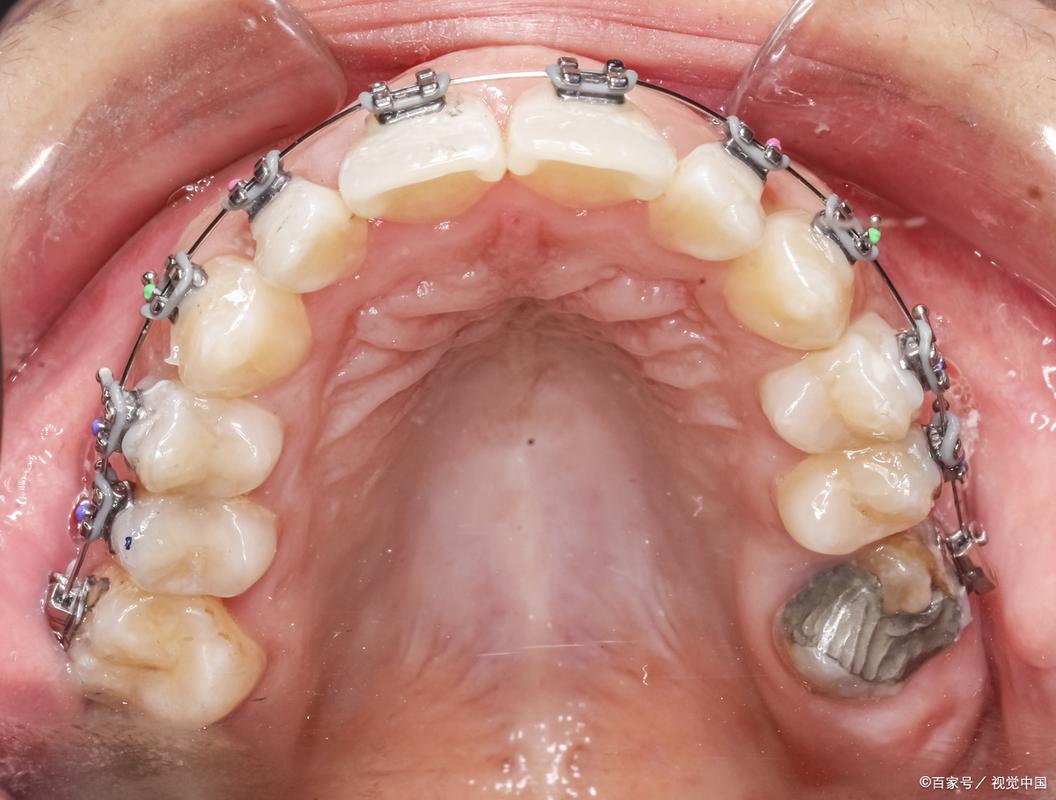

- 固定矫正:采用方丝弓矫正器或直丝弓矫正器,通过镍钛圆丝排齐牙齿,再用不锈钢方丝配合“摇椅弓”或“唇向转矩”施加力量,将舌倾的下前牙逐步向唇侧移动,此方法能精确控制牙齿移动,适合伴有轻度拥挤或咬合紊乱的患者,但需注意调整力度,避免牙根吸收。

- 隐形矫正:如隐适美、时代天使等隐形牙套,通过3D打印技术设计每副牙套的移动方案,利用持续轻柔力量将牙齿唇向移动,隐形矫正美观舒适,可自行摘戴,便于清洁,适合对美观要求高、舌倾程度较轻的患者,但需严格佩戴(每天20小时以上),疗程可能略长。